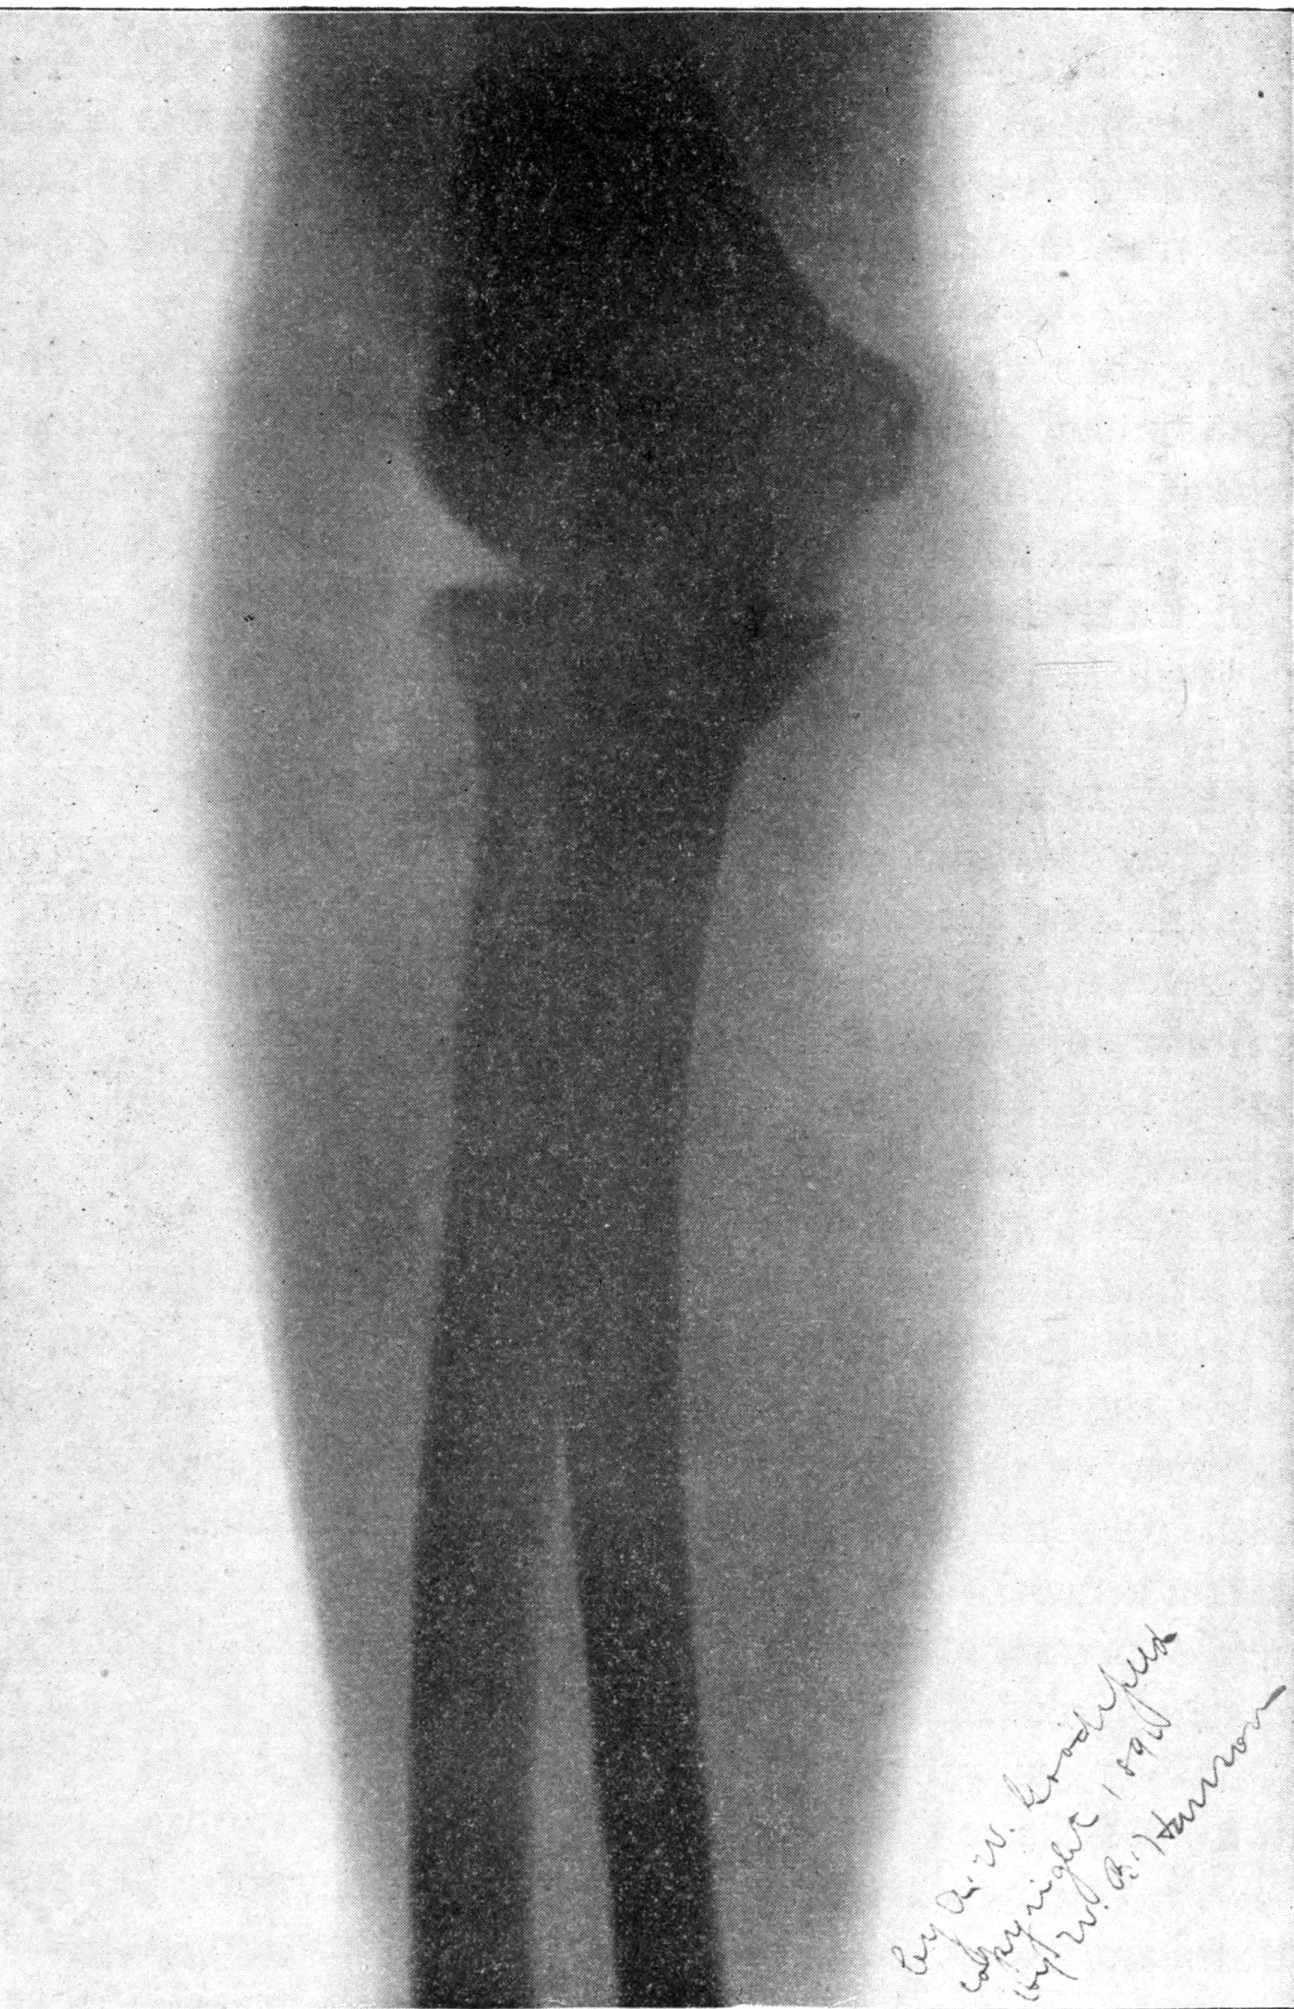

Fig. 2.—Broken Arm, Overlapping.

(Due to defective setting.)

FROM SCIAGRAPHS BY PROF. DAYTON C. MILLER. § 204.

117. Transposition of Phosphorescent Spot and of Cathode Rays without a Magnet. Salvioni, Elster, Geitel, and Tesla